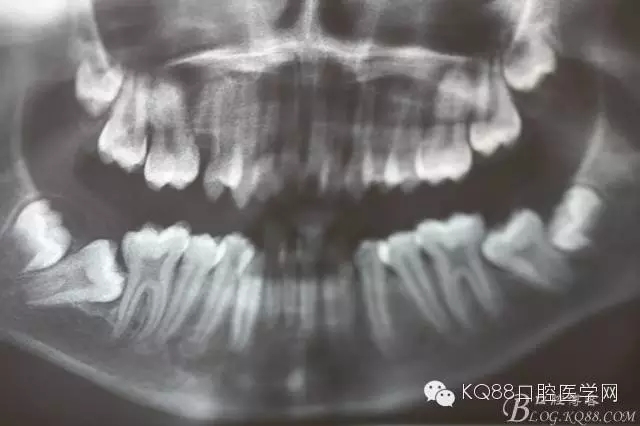

图3. 这是患者的全景片影像检查:看不清16与14之间是否有牙根遗留